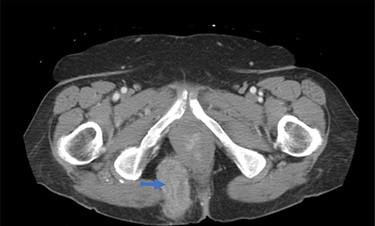

A 62-year-old post-menopausal female presented with worsening fecal urgency, incontinence and a corresponding perianal bulge that was increasing in size over the past 2 years. The patient had a recent history of significant weight loss through diet modification. Medical history was significant for two previous vaginal deliveries, 15-pack per year smoking history, hypothyroidism, hiatal hernia, previous CVA and chronic obstructive pulmonary disease. Fifteen years prior, the patient underwent a total vaginal hysterectomy, including a McCall culdoplasty, anterior and posterior repairs, sacrospinous ligament suspension and tension-free vaginal taping to treat symptomatic cystocele, rectocele and descent of the uterus. A previous computed tomography (CT) demonstrated a heterogeneously enhancing mass extending from the right posterolateral margin of the lower vaginal cuff and perirectal region into the ischioanal fossa, suggestive of, but not definite for a soft tissue mass (Fig. 1). Upon clinical exam, the patient was noted to have a defect in the right levator muscles complex with complete herniation of her rectum through this defect. This hernia created pocking of the stool and difficulties with stool emptying. In addition, the patient had to adjust her sitting position to avoid unwanted stool leakage as a result of spontaneous hernia reduction. The patient was offered an abdominoperineal resection; however, discussion of laparoscopic interventions with the DaVinci robot quickly became the best option for repair. Informed consent was obtained for robotic repair, and routine preoperative colonoscopy was performed.